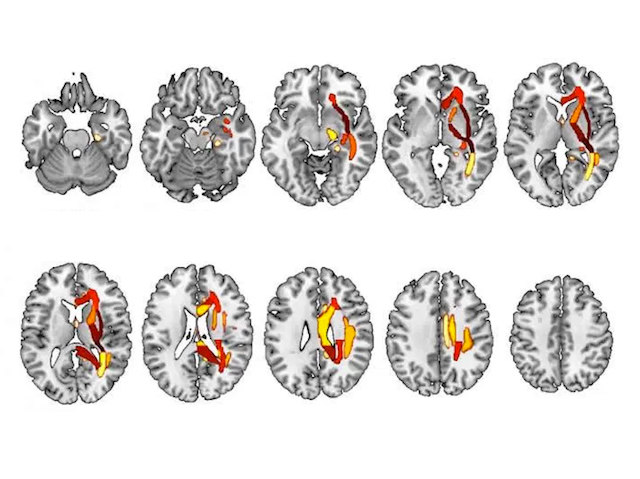

There are millions of magnetic resonance imaging (MRI) scans stored on hospital computers around the world, potentially holding clues to spotting brain conditions before they develop. Sufferers of anxiety or depression sometimes share common brain changes – patterns hidden in the bundles of nerve cells known as white matter. Here, a supercomputer running a machine learning algorithm examines MRI slices through a human brain, comparing them to other brains and learning as it goes. Common changes in the white matter associated with major depressive disorder (MDD) are highlighted in warm colours, with red showing areas of the formix, associated with memory. The clever coding can now compare future patients’ brains to these historic patterns, predicting those most at risk from MDD and, hopefully, leading to faster intervention and treatment.